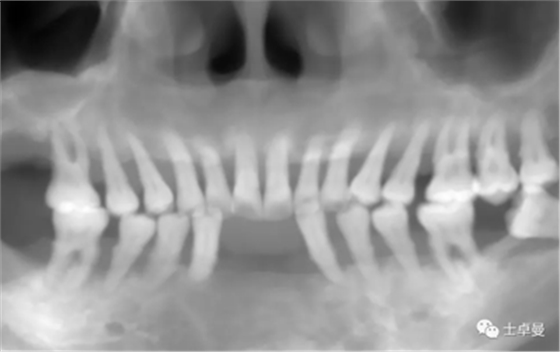

影像學檢查

CBCT檢查:顯示口內(nèi)余留牙牙槽骨吸收至根尖1/3;

上頜雙側(cè)后牙區(qū)上頜竇底可用骨高度不足;

下頜雙側(cè)后牙區(qū)下頜神經(jīng)管上方可用骨高度不足。